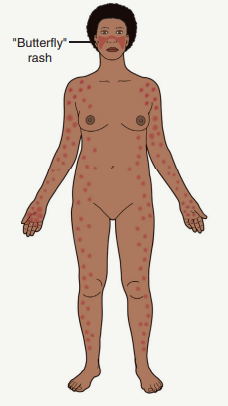

Malar Erythema: Also known as ‘butterfly rash’, the most common feature.

Malar Erythema:

Can present with varying severity from mild erythema to pronounced edema.

Associated features can include telangiectasias, erosions, dyspigmentation, and epidermal atrophy.

Common Locations:

Primarily affects the face, especially the malar region, while often sparing the nasolabial folds.

Can also spread to the hands avoiding the knuckles.

Oral ulcerations frequently occur.

The presence of telangiectasias, erosions, dyspigmentation, and epidermal atrophy aids in differentiating ACLE's malar erythema from other facial rashes.